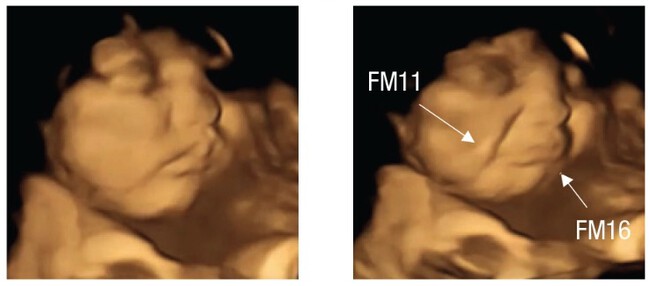

Así, podemos ver que la mayoría de los bebés expuestos al sabor de la zanahoria hacen un gesto de agrado. Estiran las comisuras de los labios, lo que solemos asociar con una sonrisa.

zanahoria Bebé antes y después de ser expuesto al sabor de la zanahoria